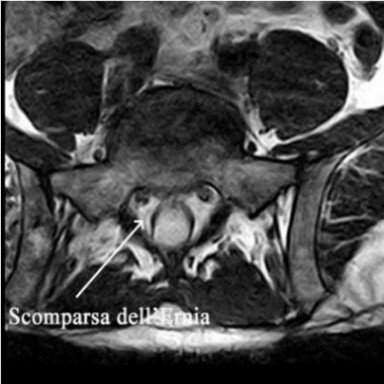

Il signore era stato operato alcuni anni fa per ernia discale lombare L5-S1 sinistra.

Dopo un periodo di benessere, aveva presentato recrudescenza di sciatalgia sinistra, che era divenuta progressivamente iperalgica invalidante, tale da costringere il soggetto al riposo a letto obbligato.

Per tale motivo aveva effettuato una risonanza magnetica del rachide lombare con evidenza di voluminosa recidiva discale L5-S1 sinistra.

Le terapie farmacologiche eseguite non avevano prodotto alcun effetto sul miglioramento del dolore.

La VAS iniziale era di 8.

Eseguiva dapprima trattamento di 2 sedute la settimana e dopo 3 settimane (6 sedute) si poteva assistere a una riduzione della VAS, che si portava a 6 e soprattutto ad una parziale ripresa degli spostamenti.

Il miglioramento è stato molto progressivo ma costante.

Dopo altre sedute con cadenza bisettimanali (10) si è passato a sedute una volta la settimana (5) ed in fine mensili (7).

Il signore a questo punto era asintomatico, eccetto che per la presenza di incostanti lievi e sopportabili parestesie al polpaccio sinistro e la sciatica era assente.

Secondo gli attuali criteri scientifici non è dimostrabile l'esclusivo rapporto tra ozonoterapia ecoguidata e la scomparsa dell’ernia.